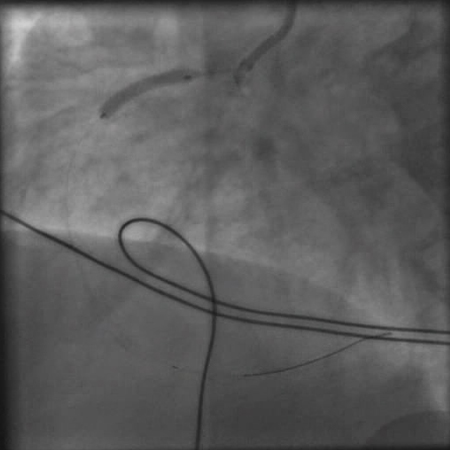

[Figure caption and citation for the preceding image starts]: Angiografia mostrando uma tentativa de abrir a artéria coronária direita obstruída com um balão de angioplastiaDo acervo pessoal do Dr. Mahi Ashwath; usado com permissão [Citation ends].